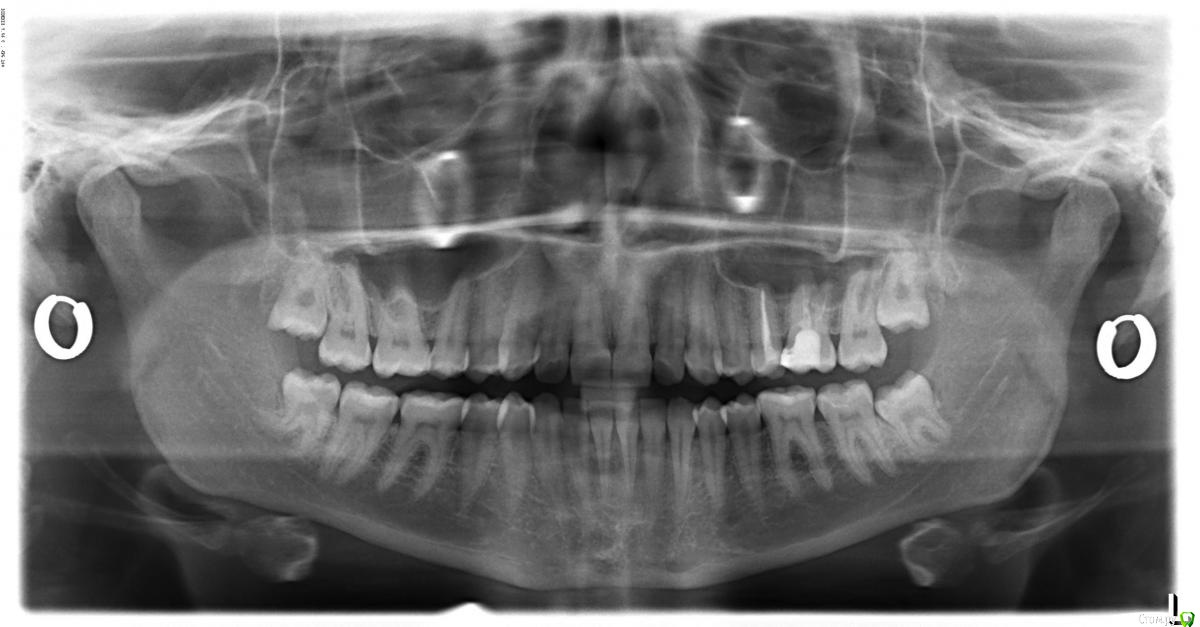

alexandrovna Опубликовано 29 марта, 2015 Автор Поделиться Опубликовано 29 марта, 2015 26 зуб все еще болит. Как советовали - сделала снимок (прикрепляю) и сходила на консультацию к другому специалисту. Вот что мне сказали, исходя из результатов внешнего осмотра (на рентгене, говорят, ничего не увидишь): 1. По 26 зубу - зуб может все еще болеть, так как предыдущий доктор не удалил сбоку временную пломбу, а просто перекрыл её (это говорил сам врач, который лечил "Она (временная пломба) так хорошо стенку зуба держит, не буду её удалять просто перекрою), поэтому нарушена герметичность (крючок застревает). Поэтому нужно перелечивать. Правда я не поняла, просто пломб переделать или каналы тоже нужно лечить (в каналах эндометазон). Переделывать у предыдущего врача не хочется, так как нет доверия и лечила мимо кассы(имела глупость).Других причин на рентгене сейчас не увидели, но сказали, что не раньше, чем через 2 месяца можно будет увидеть. 2. 15 зуб нужно срочно лечить, так как там боковой кариес на пол зуба. Внешне не видно, но там какая-то тень, которую может увидеть только специалист. 3. 45 зуб - там фиссурный кариес, но "я бы его на всякий случай вскрыла и забыла" 4. 37 и 47 зубы - кариес под пломбой. Поэтому их нужно перелечивать. Что-то из этого можно увидеть на рентгене, чтоб зря не лечить? Или просто снова довериться врачу? Сделала чистку и реминерализацию. Стало легче, действительно, зубы перестало сводить!! Спасибо! Сказали нужно еще 2 раза поставить капу. Ссылка на комментарий

red_butler Опубликовано 29 марта, 2015 Поделиться Опубликовано 29 марта, 2015 http://s018.radikal.ru/i522/1503/22/255a34ee615d.jpgтребуется повторное лечение корневых каналов зуба 2.6 с последующим протезированием Ссылка на комментарий

Гарриевич Опубликовано 29 марта, 2015 Поделиться Опубликовано 29 марта, 2015 По ОПтГ можно сказать, что 26 перелечиватьТо, что пломбировали эндометазоном тоже говорит в пользу перелечиванияА после, как уже сказал red_butler, зуб обязательно покрыть непрямой реставрацией 1 Ссылка на комментарий

Гарриевич Опубликовано 29 марта, 2015 Поделиться Опубликовано 29 марта, 2015 Для остального нужен очный осмотр и прицельные снимки Ссылка на комментарий

alexandrovna Опубликовано 29 марта, 2015 Автор Поделиться Опубликовано 29 марта, 2015 (изменено) http://s018.radikal.ru/i522/1503/22/255a34ee615d.jpgтребуется повторное лечение корневых каналов зуба 2.6 с последующим протезированием По ОПтГ можно сказать, что 26 перелечиватьТо, что пломбировали эндометазоном тоже говорит в пользу перелечиванияА после, как уже сказал red_butler, зуб обязательно покрыть непрямой реставрацией А скажите, пожалуйста, что там на снимке видно? Просто доктор сказал, что на снимке ничего плохого нет, а перелечивать надо потому, что временную пломбу не убрали и потому что болит.Спасибо! Изменено 29 марта, 2015 пользователем alexandrovna Ссылка на комментарий

alexandrovna Опубликовано 29 марта, 2015 Автор Поделиться Опубликовано 29 марта, 2015 Для остального нужен очный осмотр и прицельные снимкиНу то есть из панорамного больше ничего страшного не видно?А по прицельным снимках, без осмотра, что-то можно увидеть?Спасибо. Ссылка на комментарий

Гарриевич Опубликовано 29 марта, 2015 Поделиться Опубликовано 29 марта, 2015 сделайте прицельные снимки этого зуба, тогда будет точно яснопо ОПтГ он как будто полупустой Ссылка на комментарий